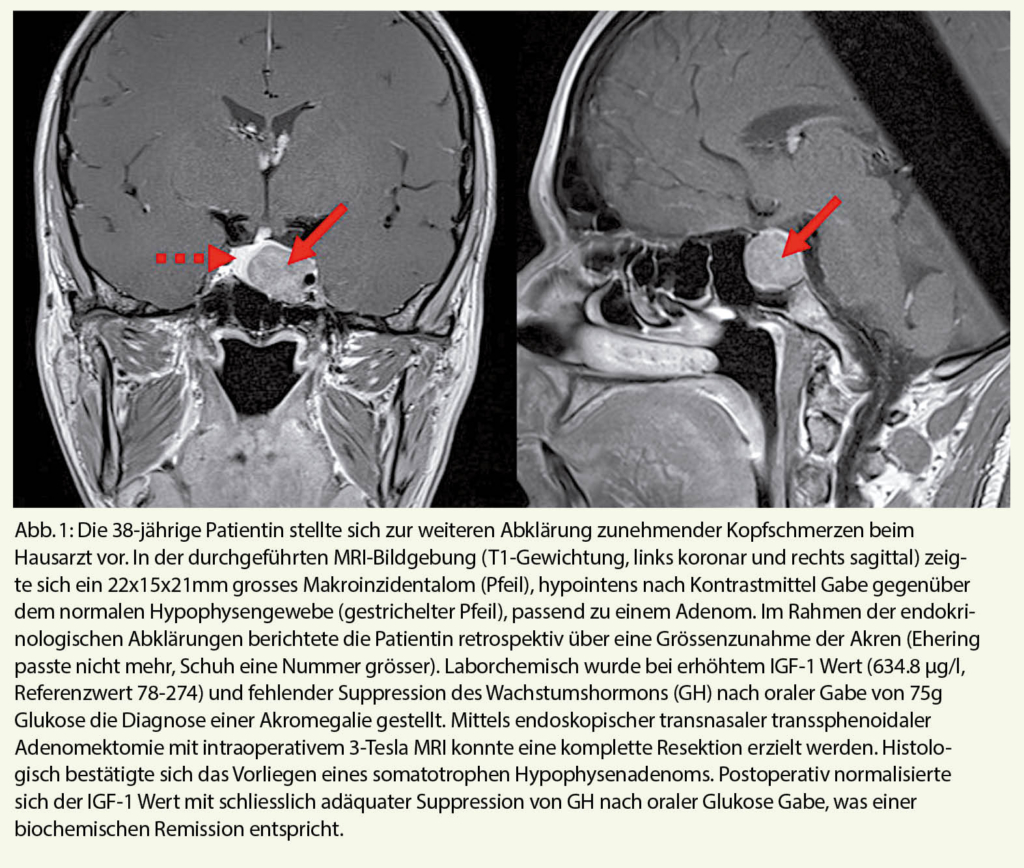

Hypophysenzindentalome sind, wie der Name suggeriert zufällig (inzidentell) nachgewiesene Veränderungen im Bereich der Hypophyse. Die initiale Bildgebung wurde somit nicht aufgrund der Vermutung einer Läsion durchgeführt. In der westlichen Ländern werden die Bildgebungen häufig im Rahmen von Kopfschmerzabklärungen (40%), gefolgt von Schädel-Hirntraumata und cerebrovaskulären Ereignissen, Sinusitiden, Abklärungen von Beschwerden der Halswirbelsäule bzw. Schwindel und Synkopen durchgeführt (1). Die Prävalenz der Hypophyseninzidentalome unterscheidet sich in den Bildgebungsserien je nach Bildgebungsverfahren und liegt bei ca. 10% (zwischen 4-38%, häufiger in den MRI-Serien gegenüber CT-Serien). Anhand der Grösse der Läsion unterscheidet man Mikro- (<1cm) von Makroinzidentalomen (≥1cm), wobei die letzteren seltener vorkommen (2). Aufgrund der steigenden Verfügbarkeit und Tendenz Bildgebungen durchzuführen in den letzten Jahren, ist eine weiterhin steigende Inzidenz von inzidentellen Hypophysenläsionen zu erwarten, wodurch der Bedarf an Wissen und Kompetenz zur adäquaten Beurteilung und für ein adäquates Management notwendig ist. In der Abbildung 1 wird ein Fall aus der interdisziplinären Hypophysensprechstunde des Universitätsspitals Zürich dargestellt.

Bei radiologischem Verdacht auf ein Kraniopharyngeom oder eine maligne Erkrankung wird eine Chirurgie angestrebt. Die Chirurgie ist ebenfalls dann die Therapie der Wahl falls ganz unabhängig von der Ätiologie des Inzidentaloms eine Kompression der Sehbahnen mit nachweisbarem neuroophtalomologischem Defizit vorliegt. Dasselbe gilt auch für Adenome mit Hormonaktivität (z.B. Morbus Cushing), mit der Ausnahme von Prolaktinomen, welche primär medikamentös behandelt werden (3, 5). Die moderne Hypophysenchirurgie hat die komplette Entfernung der Raumforderung mit Erhaltung des gesunden Gewebes und der Hypophysenfunktion sowie der neurologischen Funktionen des Patienten zum Ziel (5). Hierzu werden primär minimal-invasive Verfahren über den transnasalen und transphenoidalen Zugang bevorzugt. Diese machen heute bei Hypophysenadenomen insgesamt über 95% aller Eingriffe aus. Die transkranielle Operation hingegen wird nur in Ausnahmefällen vorgenommen, in denen der Erfolg bzw. die Risiken gegenüber einem transnasalen transphenoidalen Zugang überlegen sind, beispielsweise aufgrund der Grösse und besonderen Tumorlage (meistens supra- und parasellär). Um den Resektionserfolg zu steigern und Risiken zu minimieren, setzten moderne Hypophysenzentren auf intraoperative Neuronavigation zur Referenzierung der präoperativ durchgeführten MRI-Bildgebung, sowie den Einsatz von intraoperativen hochauflösenden MR-Bildgebung, was eine Resektionskontrolle und bei Bedarf eine Nachresektion während des Eingriffs ermöglicht (5).